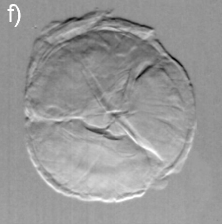

Dilute concentrations of precipitates without cores have also been observed, Figs. 3(e) and 3(f), as well as clinical cases of cataract with well-defined Y-sutures but with no distinct amounts of precipitates. In these cases, which correspond to 60% of the analyzed cases, there are significant scattering at the suture marks that can be generated either by local compaction of fiber cells or accumulation of precipitates along the marks, as for instance in Figs. 3(g) through 3(l). Refraction images show the extension of compaction areas while diffuse-scattering images can revel the presence or not of precipitates at the sutures. Absorption images (center of the analyzer window) provide essentially the same information of diffuse-scattering ones.